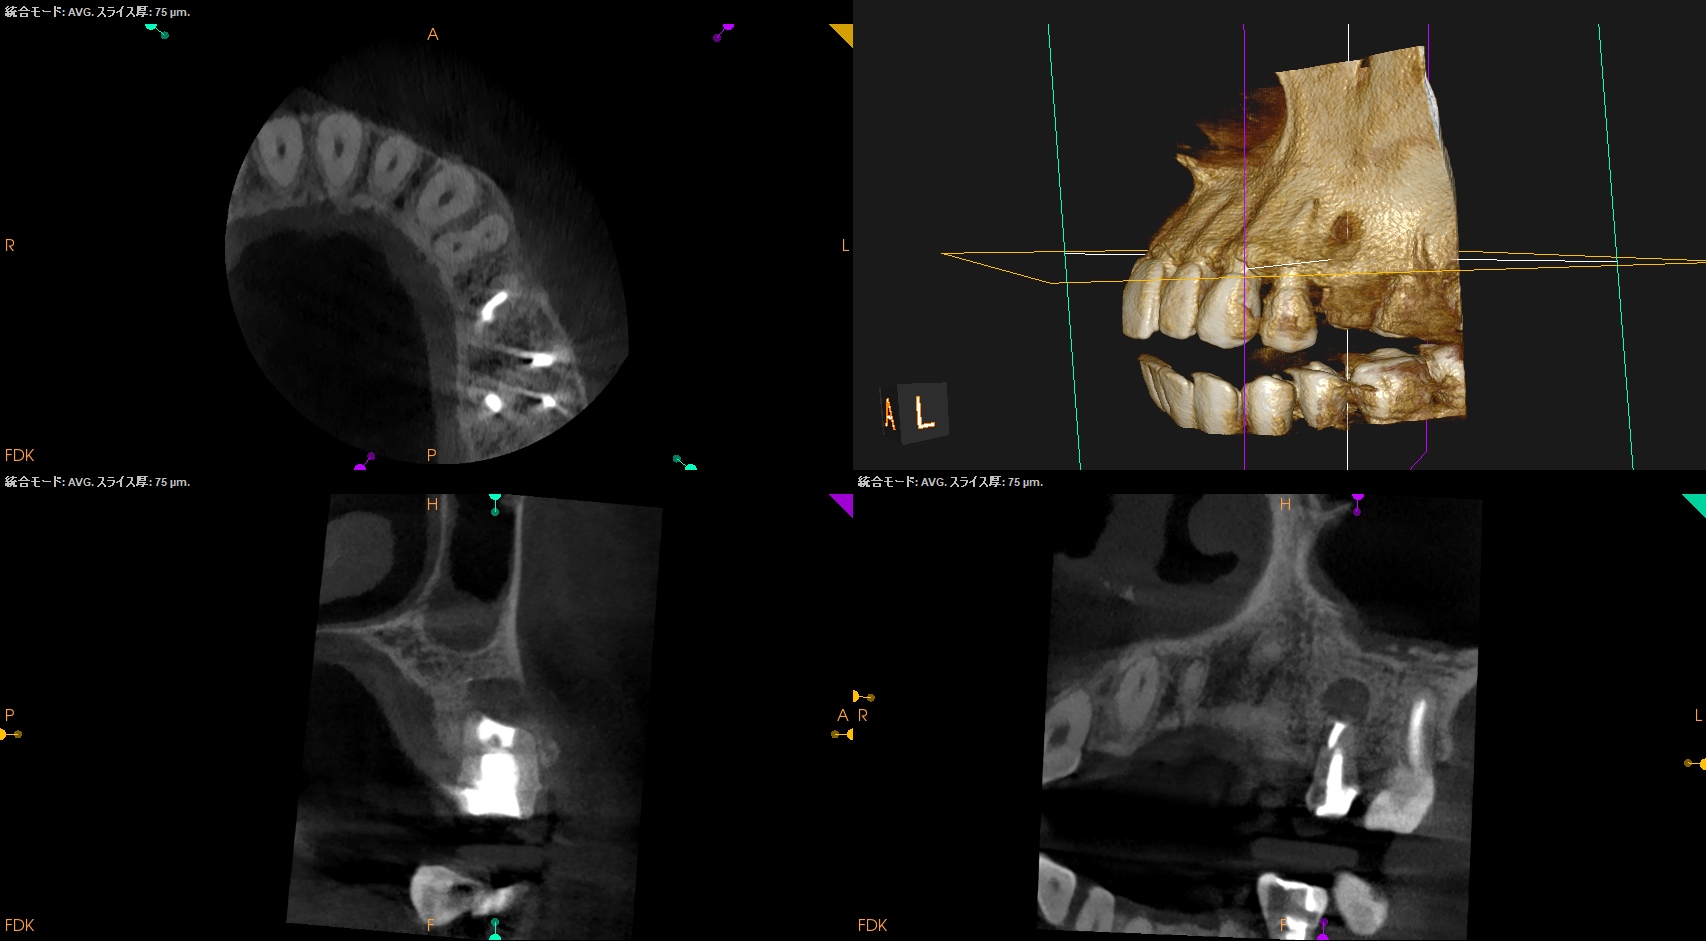

#13 Apicoectomy 5M recall(2025.12.8)

劇的に歯槽骨が回復している。

治療前・直後と5ヶ月後を比較した。